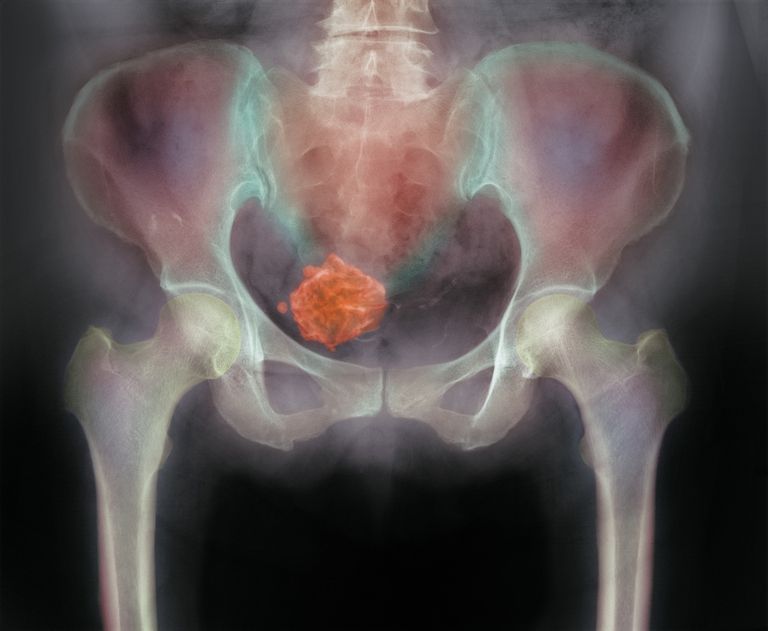

Rahimde ortaya çıkan, rahim duvarının dokusundan kaynaklanan, çapları genelde 1-15 cm arasında değişen fakat daha büyük çaplara da ulaşabilen, genellikle iyi huylu olup fakat nadiren kötü huyluya dönüşebilen tümörlerdir.

35 yaşın üzerindeki her dört kadından birinde muayene veya ultrasonla miyom saptanır.

Bu miyomlar tek olabileceği gibi çok sayıda hatta 20′ nin üzerinde de olabilir. Kadınlık hormonu olarak bilinen östrojen, miyomların büyümesine yol açar.